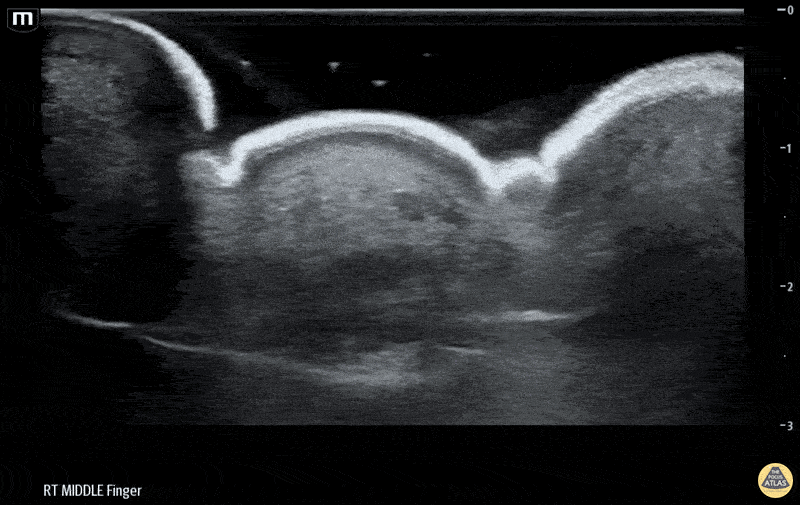

Musculoskeletal - Flexor Tenosynovitis Waterbath Ultrasound - Long axis

50 yo M presented to the ED after accidentally injuring his middle finger while welding, with reported fevers, finger swelling and all 4 Kanavel signs. Waterbath ultrasound shows fluid along the flexor tendon sheath extending distally. Hand consulted, patient taken to operative room for septic FTS. Erick Otiniano, MD MPH | DHREM PGY1 Fred Milgrim, MD | Director of Residency Ultrasound Education, Denver Health